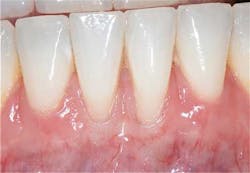

Preop: Connective Tissue Graft, Emdogain, Coronally Advanced Flap

Postop: Eight-month reevaluation